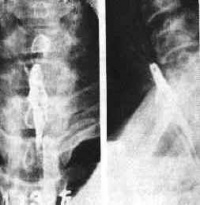

3. X线检查 对于鱼刺、肉骨等在X线下不显影的异物,应行食管钡剂X线检查,以确定异物是否存在及所在部位。对于在X线下不显影的异物,可直接作X线拍片定位。